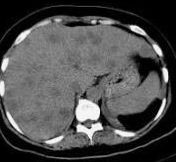

Large metastatic hepatic lesion, involving segments V, VI, VII, and part of VIII, 4.5 years after abdominoperineal resection of the rectum for poorly differentiated adenocarcinoma (Courtesy Dr. V. Penopoulos)